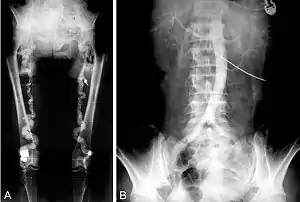

- Monckeberg's arteriosclerosis or medial calcific sclerosis is seen mostly in the elderly, commonly in arteries of the extremities.[9]